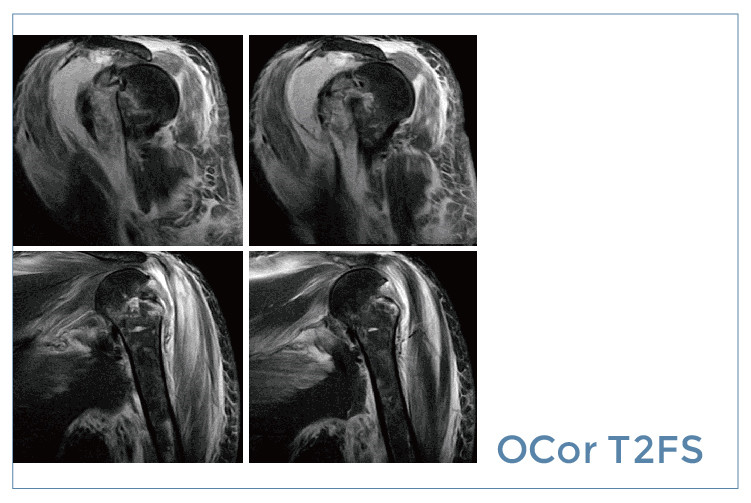

【朗润影像档案】20190830磁共振影像病例结果讨论